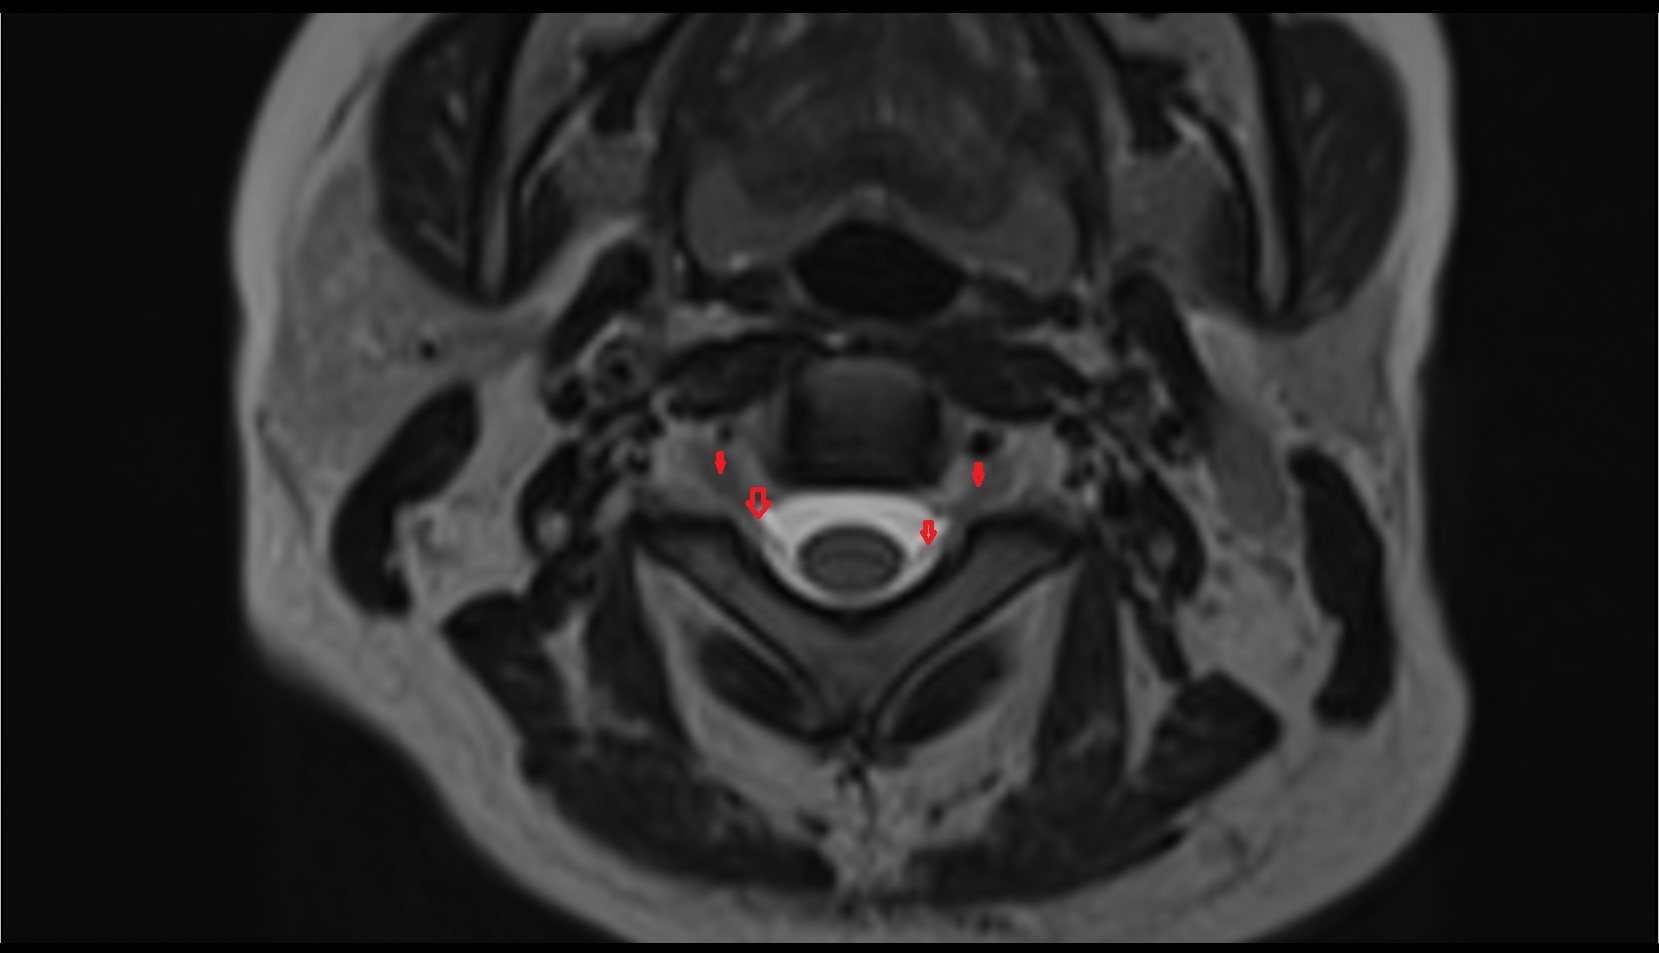

- Peripheral zone of prostate

- Anterior Fibromuscular Stroma of prostate

- Central zone of prostate

- Transitional zone of prostate